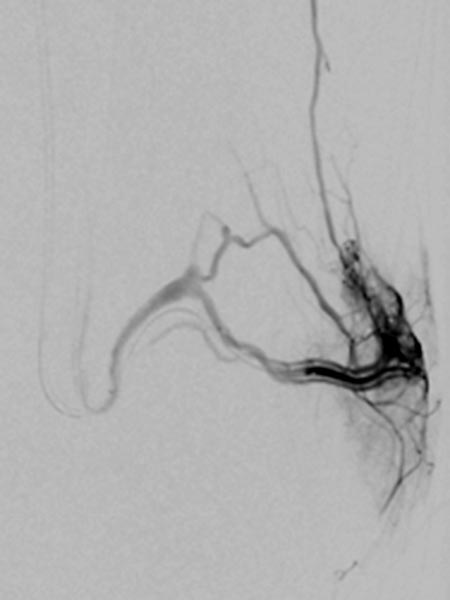

In der digitalen Subtraktionsangiographie, der Katheter liegt in der linken Arteria glutea superior, finden sich multiple, kaum identifizierbare kleine arteriovenöse Fisteln wie sie für die diffusen arteriovenösen Malformationen beim Parkes-Weber-Syndrom typisch sind.

Superselektive digitale Subtraktionsangiographie über einen Mikrokatheter in der Arteria glutea superior in einem distalen Ast. Der Nidus der feinfistulösen arteriovenösen Malformation zeigt so feine Shunts, dass diese anatomisch in der Angiographie kaum aufgelöst werden können.